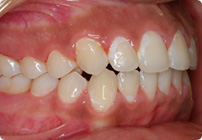

Caso: 11 años

Adolescente: Clase II

Mordida Cruzada Posterior

Sin extracción

Sin uso de expansores

6 alambres superiores

5 alambres inferiores

Sin uso de elásticos

Retenedores: Interior Fijo de TMA y Hawley en superior

Tiempo de tratamiento: 14 Visitas